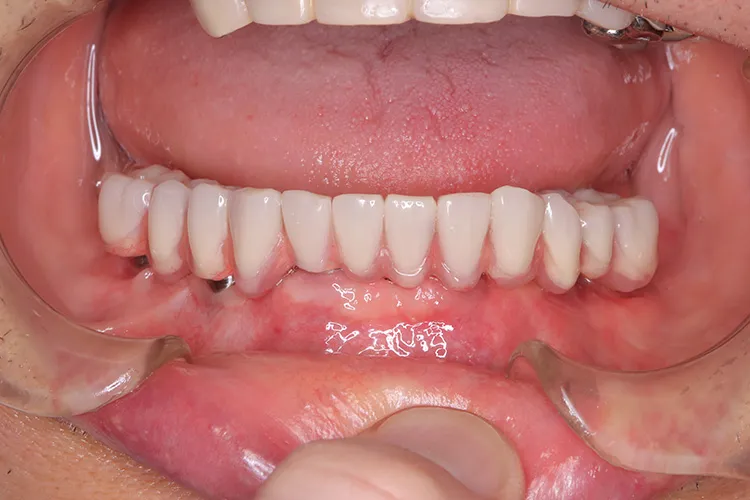

ボーンアンカードブリッジの下顎症例です。同じようにインプラント6本で上部構造を支えることができます。